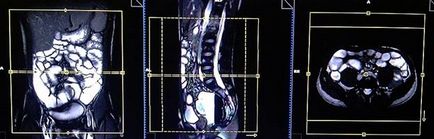

Tervezés koszorúér szeletek axiális síkban; blokk helye keresztirányban hasüregben, amint az ábrán látható. Ellenőrizze a helyét a blokk a 2 másik síkon. Ezek között a szakaszok, hogy teljesen befedje a teljes hasüreget elölről hátrafelé hasfal. A látómező (FOV) elegendőnek kell lennie, hogy fedezze a has és a medence a gyomor, hogy a szint a fancsonti. Annak megakadályozása érdekében műtermékek GDV kell használni fázist túlmintavételezésre (túlmintavételezés). Fontos, hogy a beteget a levegőt-hold alatt képrögzítő csomagokat. (A mi osztály, azt utasítják a pácienseket be és ki kétszer, mielőtt „be és tartsa vissza a lélegzetét” elején a scan).

Tervezés koszorúér szeletek axiális síkban; blokk helye keresztirányban hasüregben, amint az ábrán látható. Ellenőrizze a helyét a blokk a 2 másik síkon. Ezek között a szakaszok, hogy teljesen befedje a teljes hasüreget elölről hátrafelé hasfal. A látómező (FOV) elegendőnek kell lennie, hogy fedezze a has és a medence a gyomor, hogy a szint a fancsonti. Annak megakadályozása érdekében műtermékek GDV kell használni fázist túlmintavételezésre (túlmintavételezés). Fontos, hogy a beteget a levegőt-hold alatt képrögzítő csomagokat. (A mi osztály, azt utasítják a pácienseket be és ki kétszer, mielőtt „be és tartsa vissza a lélegzetét” elején a scan).